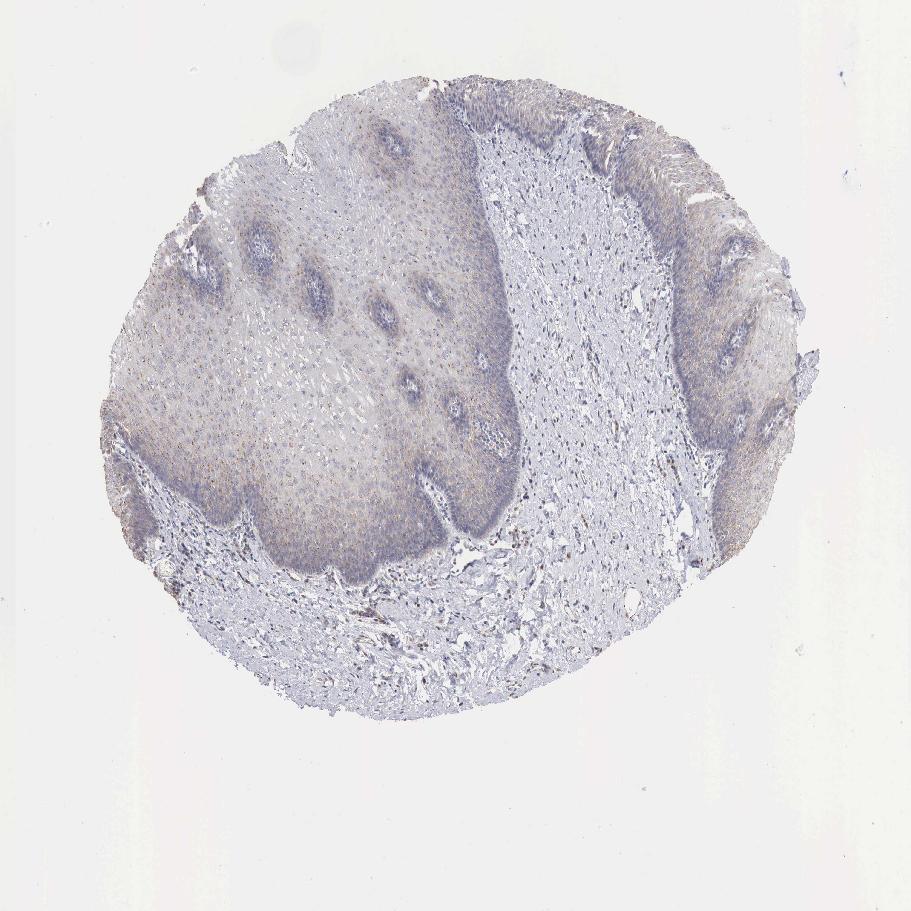

ESOPHAGUS - Antibody stainingi

Antibody staining in the annotated cell types in the current human tissue is reported as not detected, low, medium, or high, based on conventional immunohistochemistry profiling in selected tissues. This score is based on the combination of the staining intensity and fraction of stained cells.

Each image is clickable and will lead to virtual microscopy that enables deeper exploration of all samples and also displays staining intensity scores, fraction scores and subcellular localization as well as patient and tissue information for each sample.

Antibody HPA000175

Squamous epithelial cells Medium